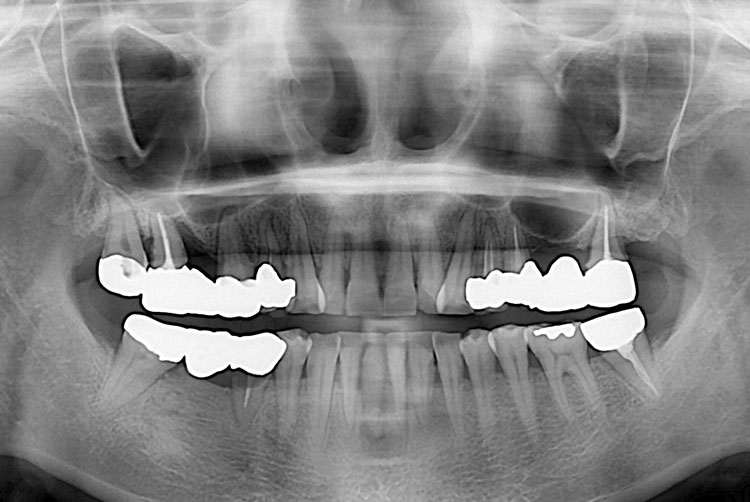

[임플란트] 임플란트

치료전 : 2018-03-20